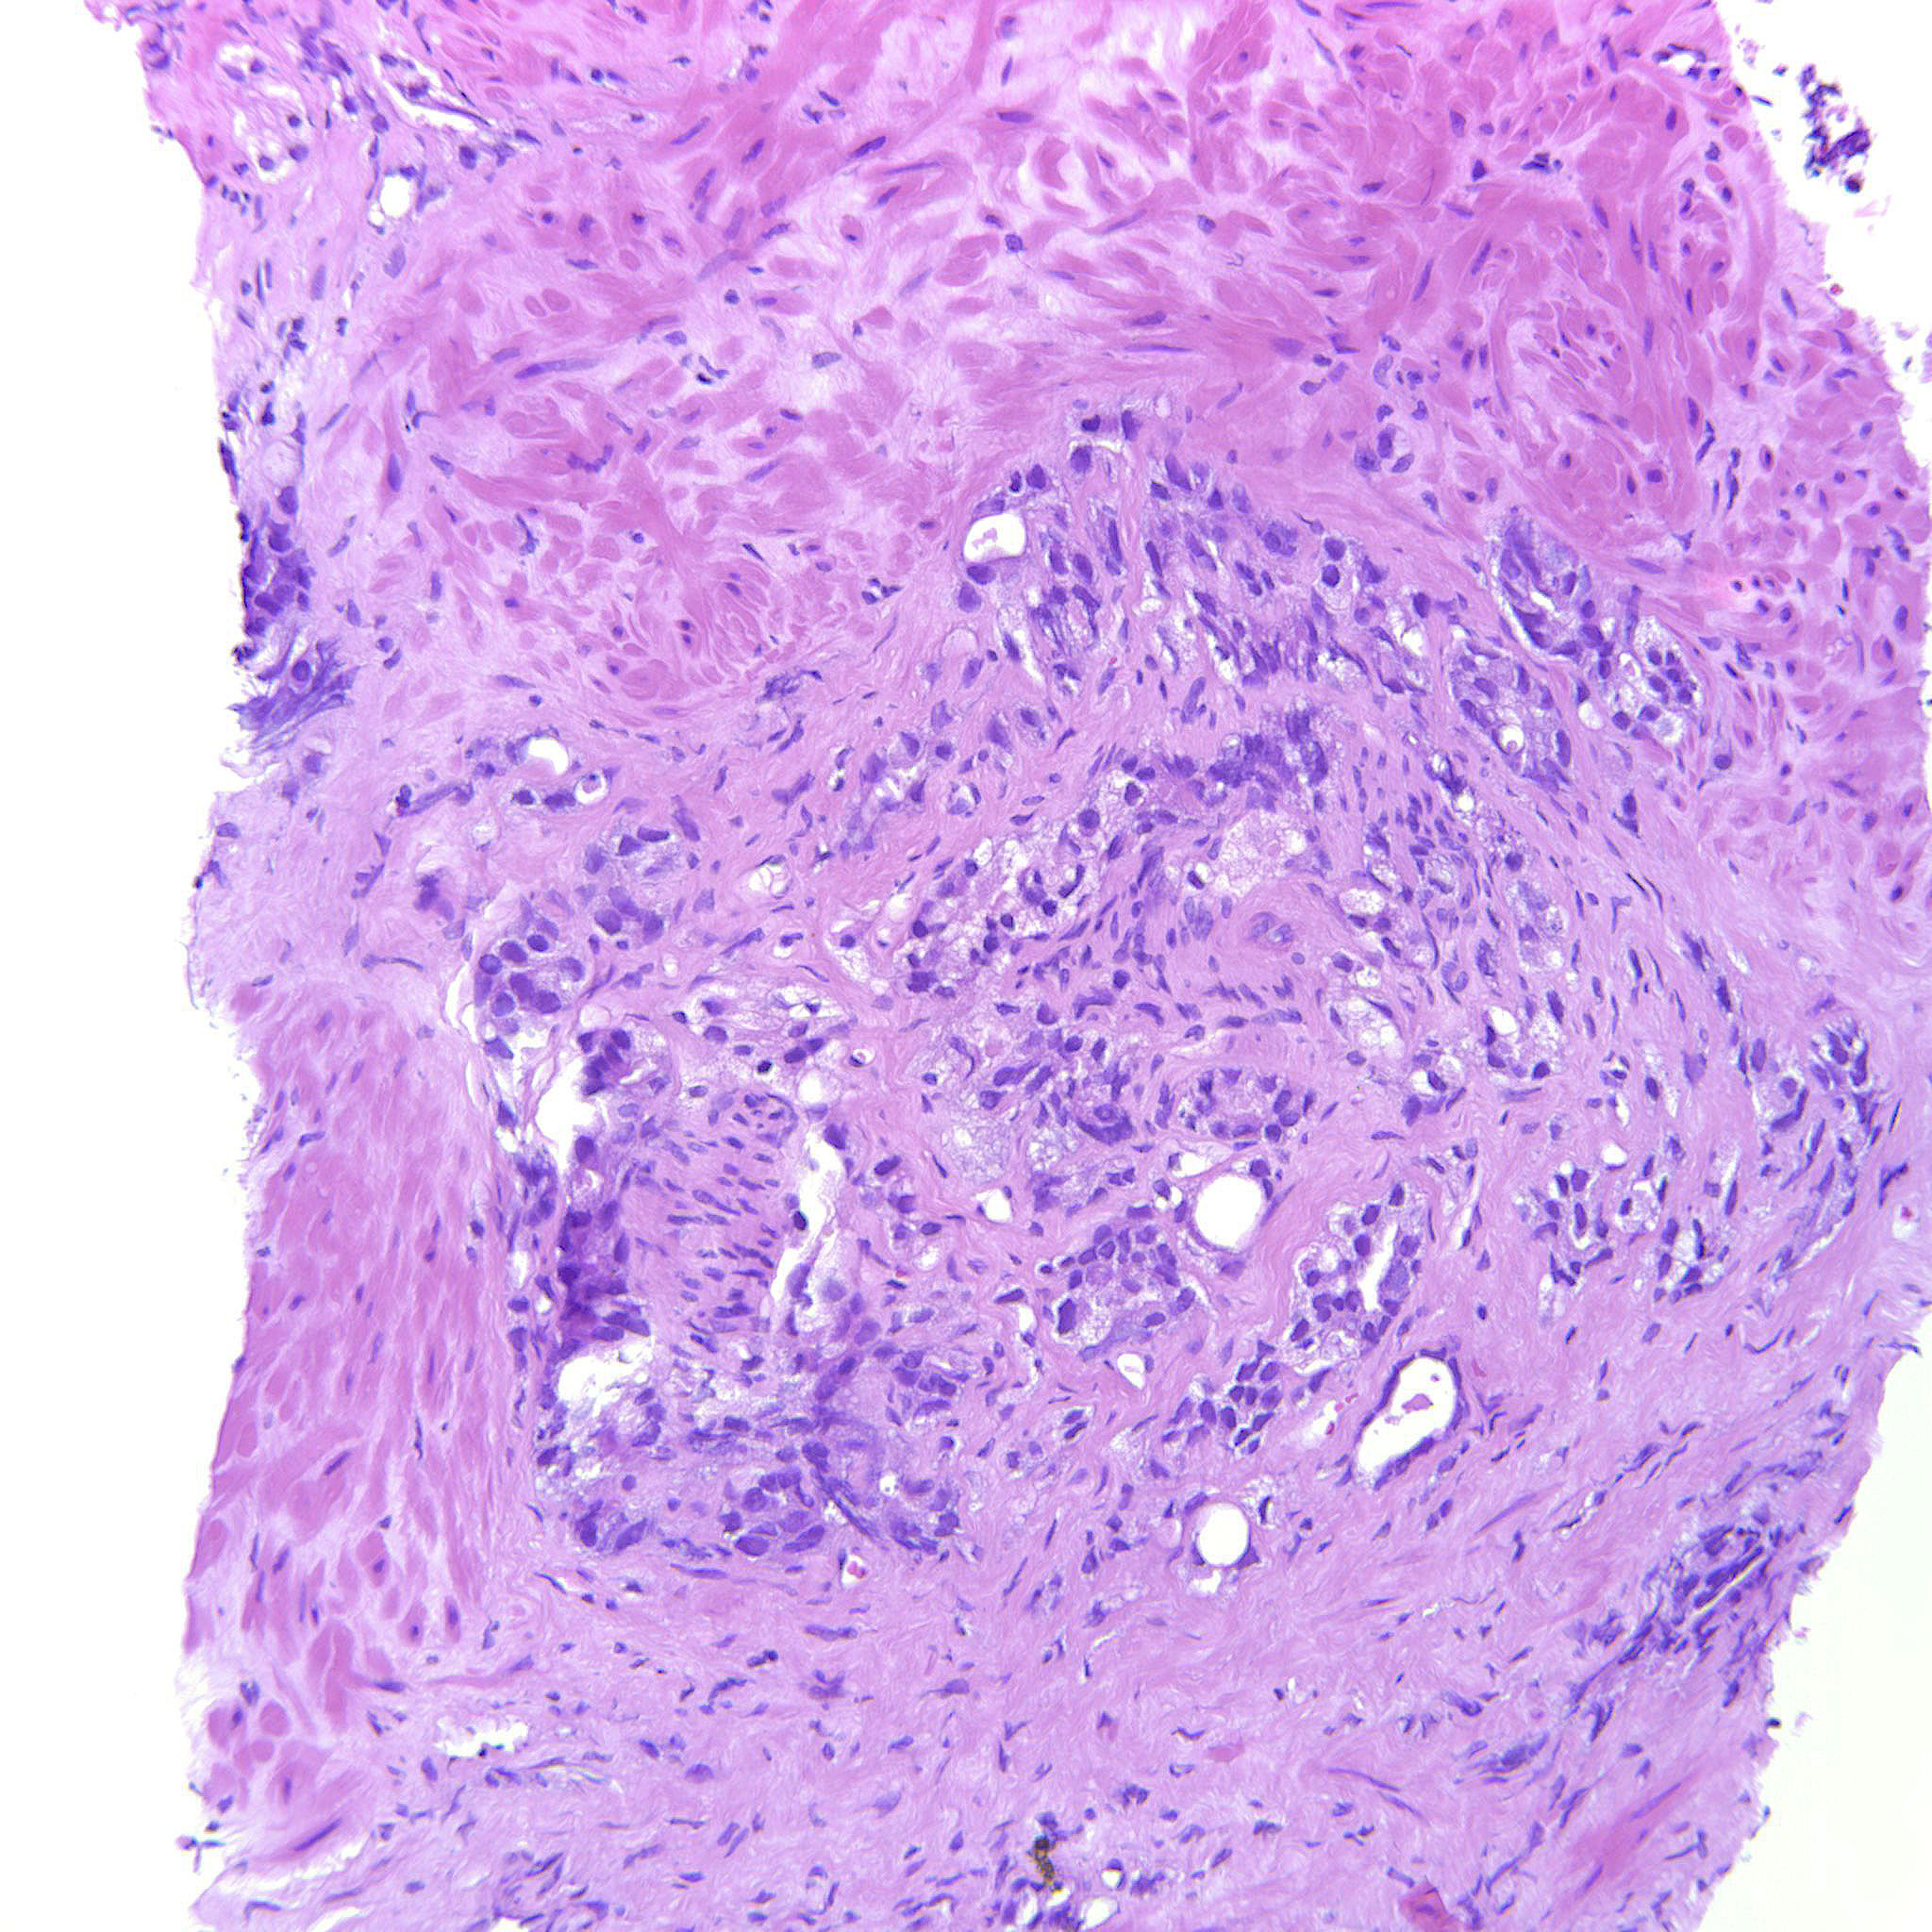

Prostate cancer grading

Case ID: 635